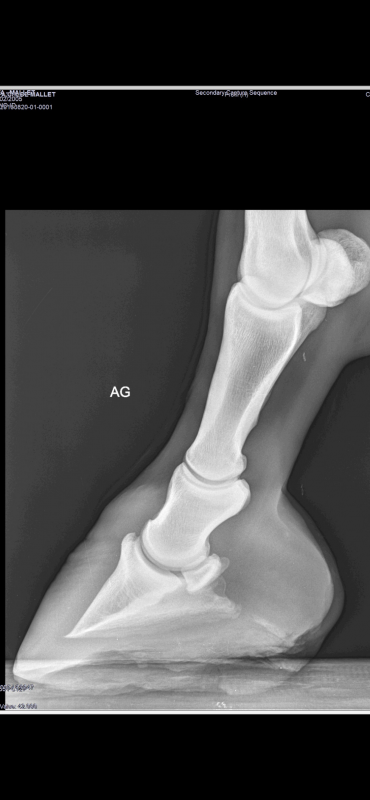

Voilà les dernières radios de ma jument. Ainsi que ses pieds actuellement :

Les pieds de ta jument sont pas beaux du tout. Les talons sont serrés et hauts. Il y a peut être 1cm de talons en trop et les barres sont très orientées vers la verticale, elles empêchent complètement la distorsion de l'arrière du pied.

C'est un parage intrusif mais de mon point de vue et sur plusieurs cas, j'ai trouvé très efficace ! Là ta jument n'a pas eu de grosse bascule de phalange donc tu peux y aller, en descendant les talons en deux fois pour être précautionneux, je ne pense pas qu'elle souffrira de ses boulets